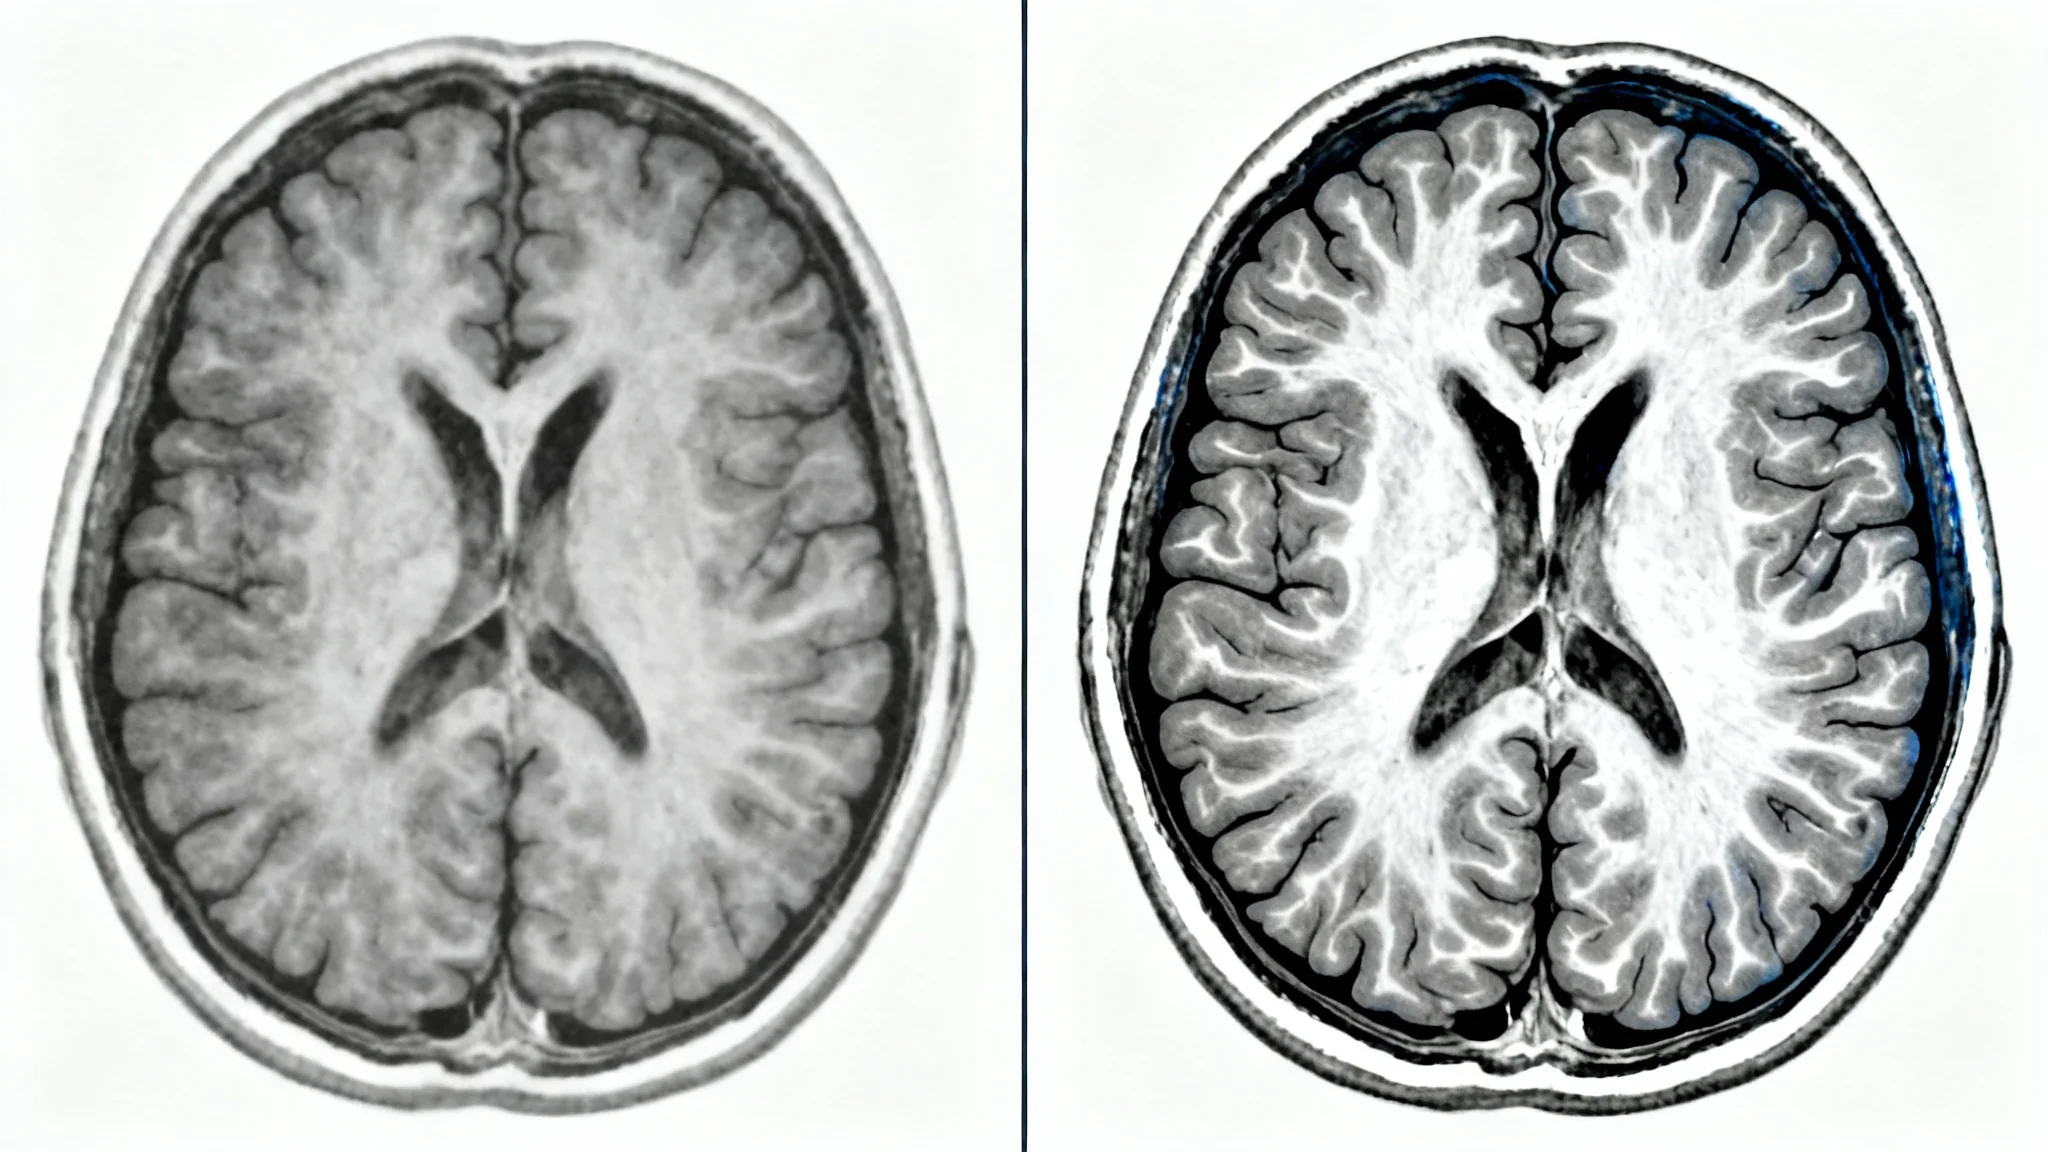

A side-by-side comparison of an MRI brain scan. The left image is a standard, low-contrast scan. The right image is a high-contrast, enhanced version, showing sharp details and highlighted areas, illustrating the effect of MRI contrast enhancement.

Reduce the time spent on manual image adjustments and post-processing. Pixelcut’s AI agent streamlines the enhancement process, delivering a high-quality, contrast-enhanced scan in moments. This efficiency allows medical professionals to focus more on analysis and reporting rather than on image manipulation. By automating a key step in the imaging pipeline, our tool helps accelerate the entire diagnostic workflow, from scan acquisition to final report, enabling faster delivery of crucial information.